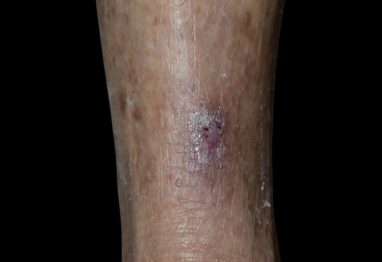

鱗狀細胞癌 (Squamous Cell Carcinoma)

這是第二常見的皮膚癌,比基底細胞癌更容易擴散及侵犯周圍的組織,但也相對比較少見。它可能表現為紅色、鱗狀的斑塊,或是一個結痂、粗糙的腫塊。